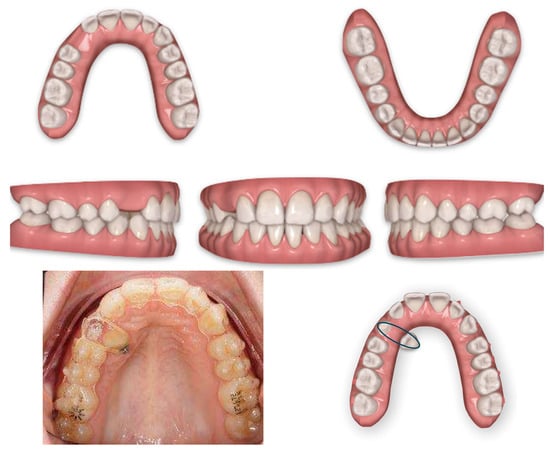

The panoramic X-ray showed unilateral permanent canine displacement in sector four with an alpha angle of more than 53° degrees according to the Ericson and Kurol classification (Figure 2).

Figure 2.

Pre-treatment panoramic X-ray with the evaluation of alpha angle and sector according to the Ericson and Kurol classification.